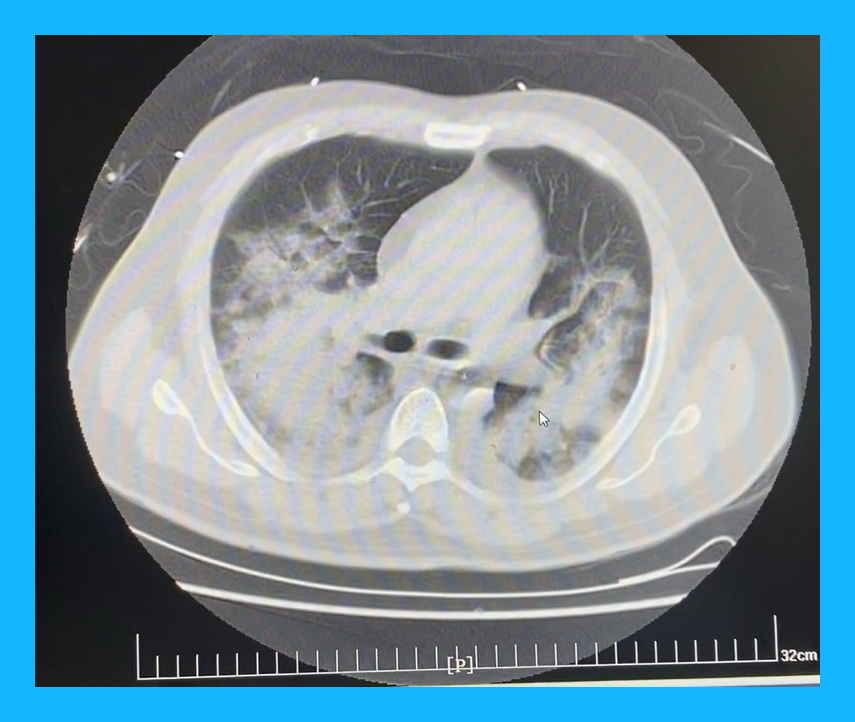

急性心肌梗死心脏破裂在急性期手术,由于心肌处于严重的炎症水肿状态,早期很多病人因此造成切口出血下不了手术台;美国STS数据库显示,如果在发病4周后手术,患者的病死可能性为13.2%,所以目前大多数倾向择期手术;但临床中只有5%的患者可以保持血流动力学稳定,所以急诊手术是唯一有效的救命方法;而这个患者更为严重的是,由于没有及时就医,双肺严重水肿,X片上双肺已经全部发白,血压只能靠IABP勉强维持。

ICU团队高度重视患者病情,时刻关注患者的入液量、尿量、循环情况,每日多次行床旁超声评估病情,患者血压逐渐平稳,升压药物逐渐减量,肺功能明显改善,顺利拔除了气管插管,患者各项指标情况逐渐恢复正常。